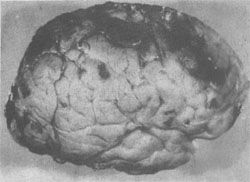

缺血性脑病的常见类型:①层状坏死。大脑皮质第3、5、6层神经元坏死、脱失、胶质化,引起皮质神经细胞层的中断。②海马硬化。海马锥体细胞损伤、脱失、胶质化。③边缘带梗死(图16-20)。梗死的范围与血压下降的程度和持续的时间有关,如血压持续下降,则梗死区自远心端向次远心端扩大,称为向心性发展(cardiopetal development),即C形梗死区向其两侧扩大,并自大脑顶部向颅底发展。大脑缺血性脑病边缘带梗死的极端情况是全大脑的梗死,但脑干的各核团由于对缺血(氧)的敏感性较低仍可存活。患者靠呼吸器以维持生命,但意识丧失,成为植物人。如何处置这样的病人则成为目前医学伦理学和医疗实践的难题。一旦这种病人死亡,其大脑乃成为由脑膜包裹,秽暗无结构的坏死组织,称为呼吸器脑。

大脑缺血性脑病

图16-20 大脑缺血性脑病

大脑前、中、后动脉血供边缘带出血性梗死灶呈C形